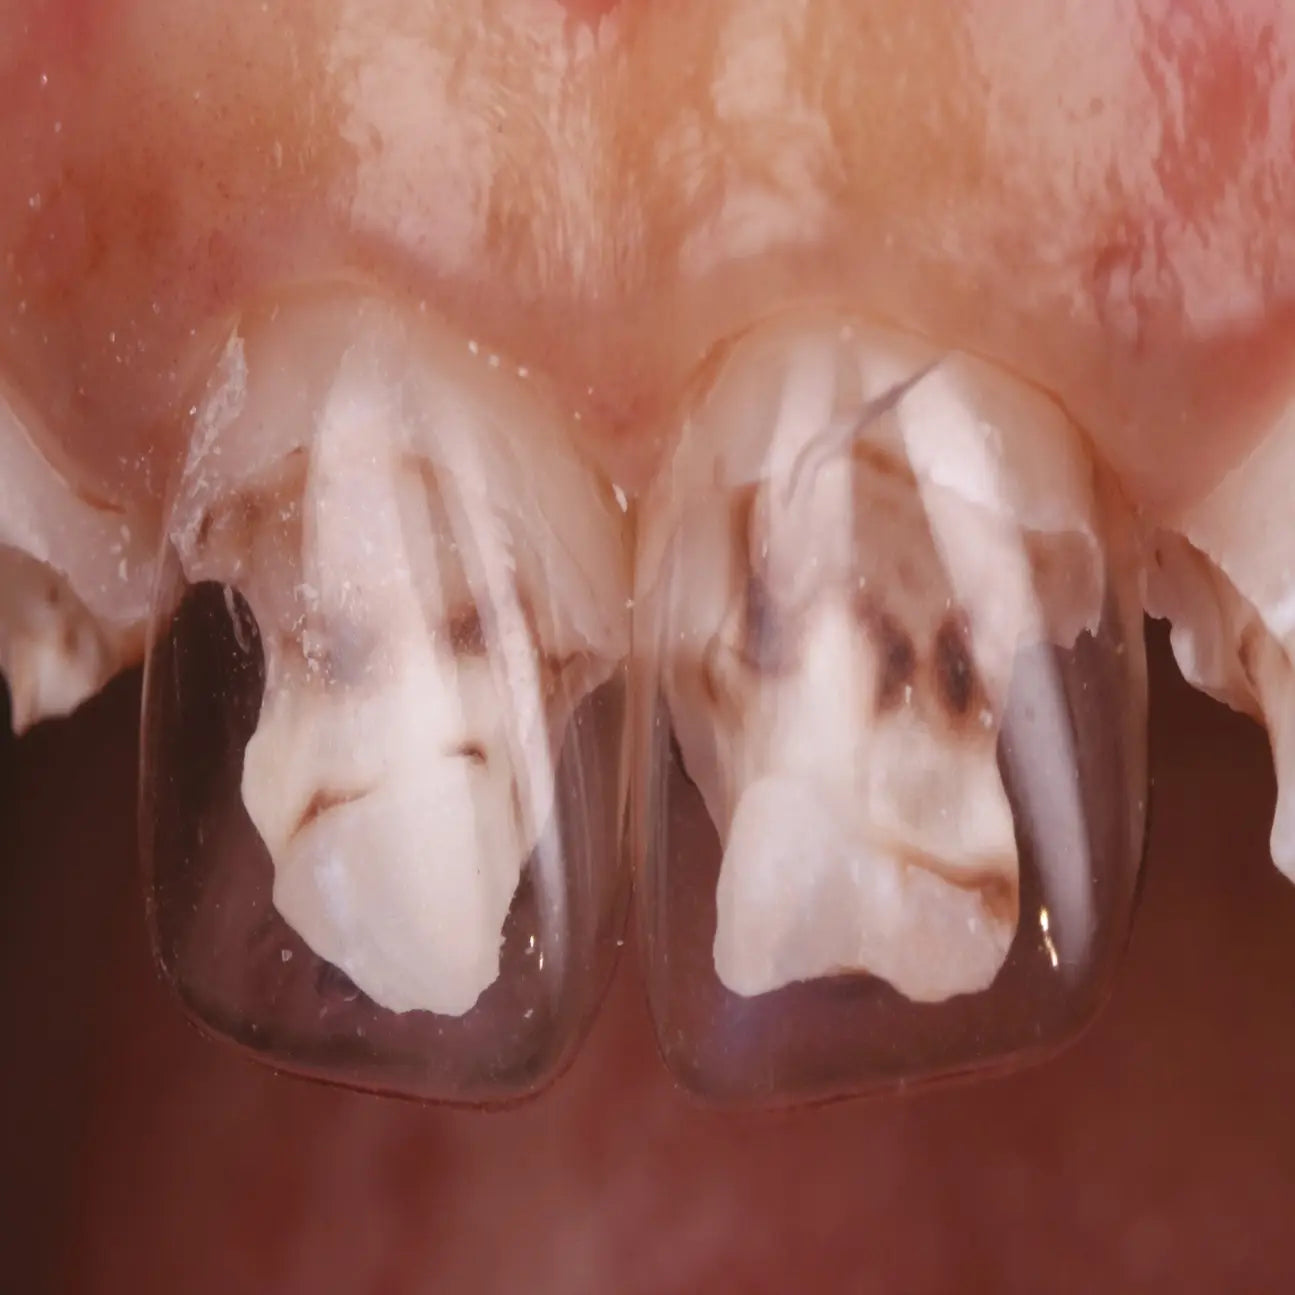

Pédodontie

La pédodontie est une spécialité essentielle qui vise à prendre en charge la santé bucco-dentaire des enfants, de la petite enfance à l’adolescence.

Plus qu’une simple adaptation des soins de l’adulte à l’enfant, elle demande une approche spécifique, à la fois médicale, psychologique et éducative, pour instaurer une relation de confiance durable avec le jeune patient et ses parents.